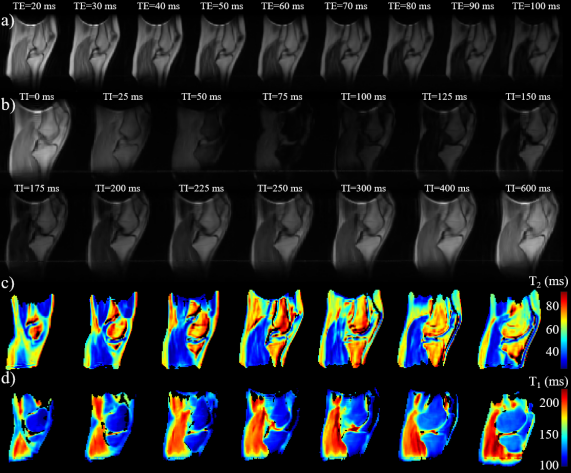

For the measurement of T2T_{2} in the soft tissues of the knee following a standard approach (Sec. II-G), a series of RARE images were acquired with TRT1\text{TR}\gg T_{1}. The echo time (TE) was progressively varied in steps of 10 ms, from TE=20\text{TE}=20 ms up to 100 ms, at which point the signal of all tissues became strongly attenuated. For the measurement of T1T_{1}, fourteen STIR images were acquired with TRT1\text{TR}\gg T_{1}, varying the inversion time (TI) from TI=0\text{TI}=0 up to TI=600\text{TI}=600 ms, where the signals of all tissues were fully recovered from inversion.

The results presented below correspond to the standard procedures described in Section III-E for T1T_{1} and T2T_{2} mapping.

Refer to caption

Figure 6: Quantitative T1T_{1} and T2T_{2} maps obtained using gold-standard methods. (a) Single slice containing the posterior cruciate ligament from a series of nine RARE images acquired at varying echo times (TE). (b) Same slice from a series of fourteen STIR images acquired at varying inversion times (TI). (c) T2T_{2} map computed from the data in (a). (d) T1T_{1} map computed from the data in (b).

Figure 6a shows a representative slice from a series of nine 3D RARE images of a healthy volunteer’s knee, acquired with echo times ranging from 10 ms to 100 ms. Figure 6b shows the same slice from a series of fourteen 3D STIR images acquired in another healthy volunteer, with inversion times ranging from 0 ms to 600 ms. Figures 6c and d display the corresponding T2T_{2} and T1T_{1} maps of the knee’s soft tissues, obtained by voxelwise fitting of the signal variation with TE and TI according to Eqs. (9) and (10), respectively.